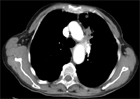

Clinique : femme de 31 ans, céphalées depuis 2 mois, parésie du membre supérieur droit.

Quel est votre diagnostic ?

Imagerie IRM conventionnelle :

Lésion frontale gauche cortico-sous-corticale, relativement bien limitée, en hypersignal FLAIR hétérogène avec petites zones nécrotico-kystiques en profondeur. Œdème périlésionnel modéré, mais effet de masse tumoral notable sur les sillons adjacents et la ligne médiane.

La masse est hypointense en T1. Prise de contraste nette, hétérogène, prédominante en zone profonde après injection